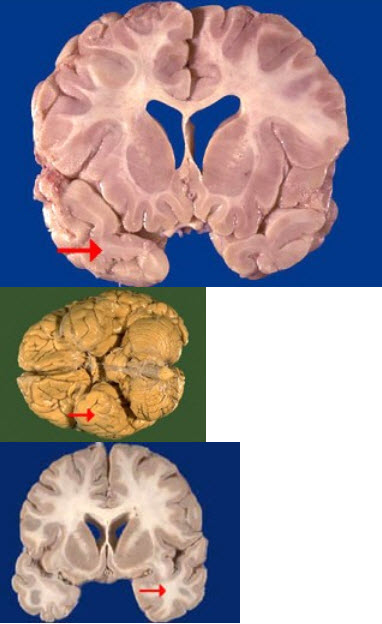

如图箭头所示为大脑哪个部位( )

A:额叶

B:颞叶

C:枕叶

D:顶叶

E:岛叶